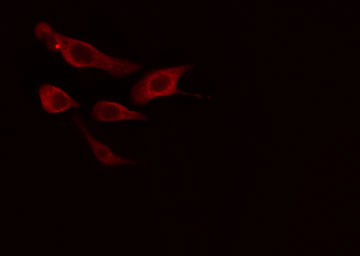

IF (Immunofluorescence)

(AAA324260 staining HT29 cells by IF/ICC. The sample were fixed with PFA and permeabilized in 0.1% Triton X-100, then blocked in 10% serum for 45 minutes at 25 degree C. The primary antibody was diluted at 1/200 and incubated with the sample for 1 hour at 37 degree C. An Alexa Fluor 594 conjugated goat anti-rabbit IgG (H+L) antibody, diluted at 1/600, was used as secondary antibody.)